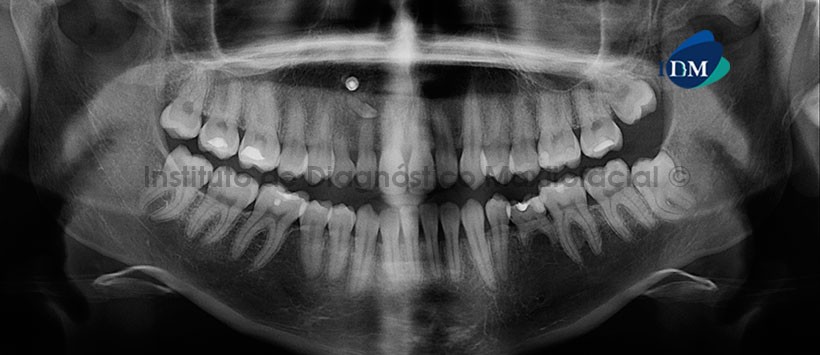

A la evaluación de la radiografía panorámica, lo más resaltante es la persistencia de la pieza 53 la cual cuenta con una reabsorción radicular externa, a su vez se observa un aditamento de densidad metálica proyectada a nivel de zona periapical de las piezas 12 y 53. También se pudo detectar un diente supernumerario (microdiente) el cual su segmento coronario se proyecta sobre el ápice de la pieza 12. Cabe mencionar que, así como la pieza 53, la pieza 75 también está en persistencia motivo por el cual nos da un indicio de agenesia de la pieza 35. (Figura 1)